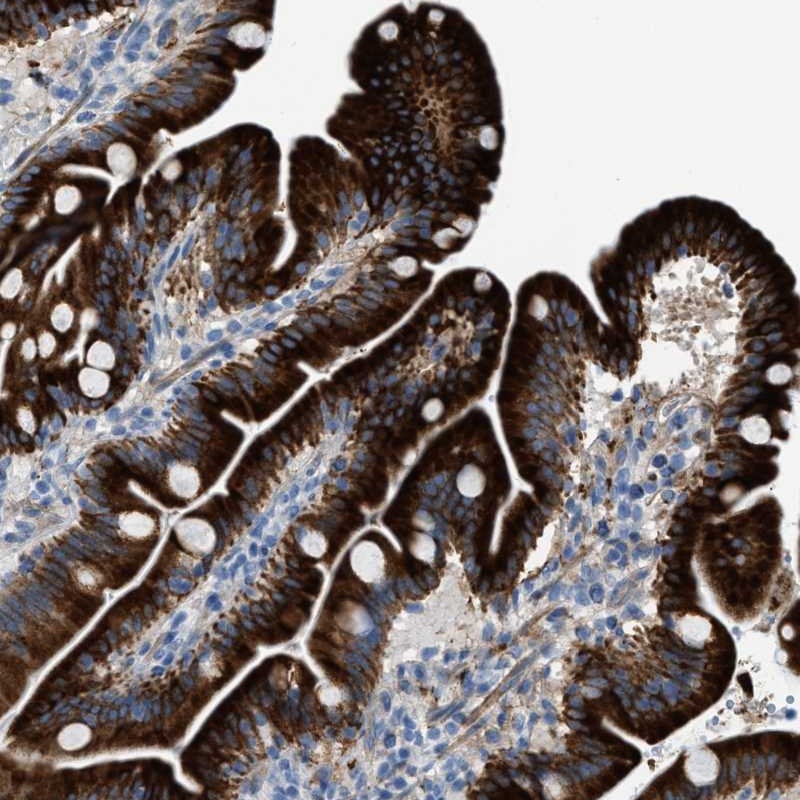

Immunohistochemical staining of human duodenum shows strong cytoplasmic positivity in glandular cells.